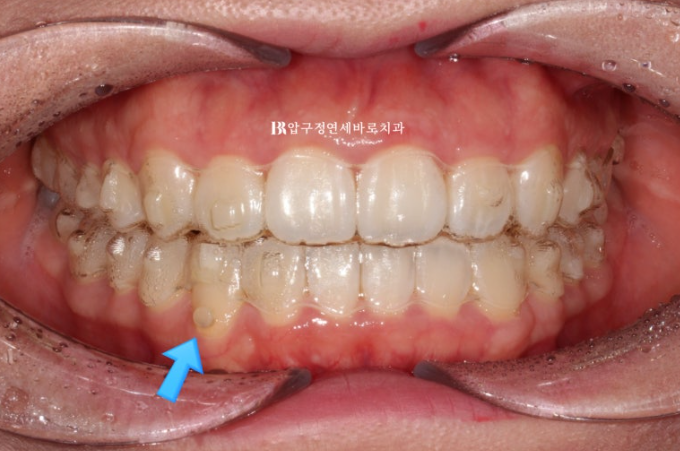

24.04

추가장치 14개를 4개월에 걸쳐 다 낀 후 모습입니다.

중심선이 맞아지고

송곳니 반대교합이 완벽하게 개선되었습니다.

돌출되어 뻗쳐있던 앞니 각도가 개선이 되면서 돌출감이 개선되었습니다.

23.07-24.04

순서대로 23.07 초진 - 23.11 1차세트 후 재제작 - 24.04 치료 종료

총 치료기간은 중간에 장치 주문 후 기다리는 시간을 제외하면 실제 8개월 입니다.

치간삭제로 윗니 가운데 블랙트라이앵글도 없어졌습니다.